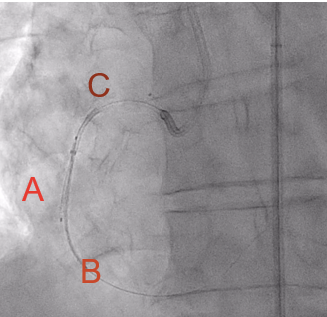

In view of this complication and the clinical instability of the patient, extraction of the device with a coronary snare was attempted but was unsuccessful (Figure 3). The access route was then changed to the femoral artery using an Amplatz left 6F catheter, and a Sion guidewire was advanced to the distal segment of the right coronary artery with the support of a 135-cm FineCross microcatheter (Terumo). This was followed by dilatation using a Sapphire II PRO balloon (OrbusNeich) (Figure 4) with catheter extension and anchoring of the balloon until 2 new everolimus-eluting stents (2.5 x 40 mm and 3.0 x 15 mm) could be advanced (Figure 5). Upon post-dilation of the noncompliant balloon, the previous stent and ballon were successfully crushed, obtaining a good final angiographic result (Figure 6). The procedure was completed with intracoronary optical coherence tomography, which confirmed adequate stent expansion and apposition, as well as the crushing of both the stent and the previous balloon (Figures 7-11).